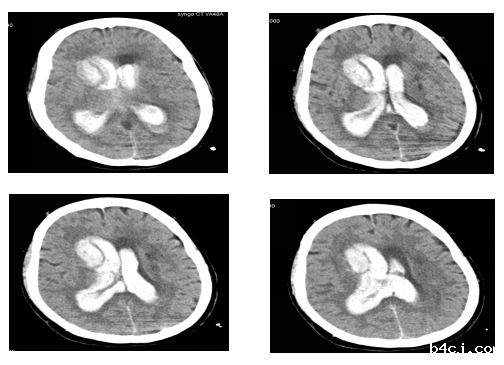

患者被送到我院时,已经是昏迷状态了,属于严重意识障碍。神经外科专科会诊后,马上安排了急诊手术。经过积极手术抢救和术后的精心治疗,王阿姨的病情得到了很好的恢复,可以正常行走、交流和进食,现已顺利出院。